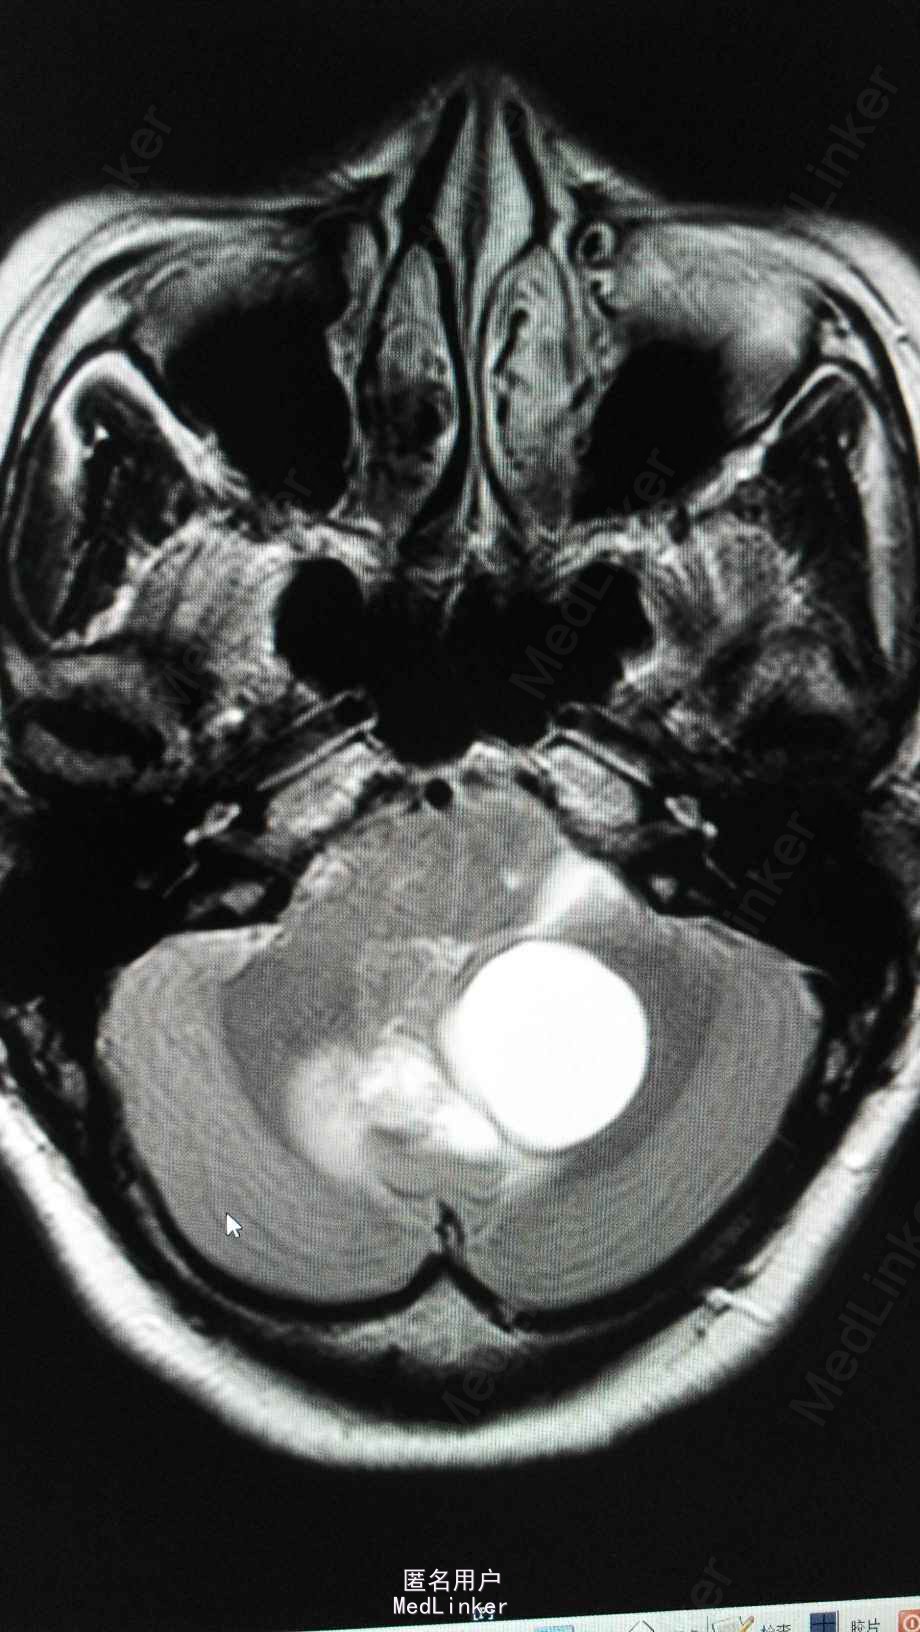

头颅MRA:小脑蚓部占位,血管母细胞溜可能性大;左椎动脉颅内段局部轻度狭窄;左侧大脑前动脉A1段稍细。

von Hippel-Lindau(VHL)综合征是一种罕见而危害严重的常染色体显性遗传病,表现为家族性多发性多器官性良恶性肿瘤症候群,发病率约1/36 000,患者多在18—30岁出现症状,其表现复杂多样,目前已发现位于14个脏器的40种不同病变,其中包括中枢神经系统(CNS)血管母细胞瘤(HB)、视网膜HB、嗜铬细胞瘤、肾细胞癌、肾囊肿、胰腺内分泌肿瘤、胰腺囊肿及内淋巴囊肿瘤等¨。VHL相关肿瘤中最常见者为CNS.HB,25%~40%,CNS—HB与VHL综合征有关。VHL综合征的病死率和致残率均较高,但由于对VHL综合征的认识尚不足,大多数病例漏诊。加强对确诊和可疑患者进行定期全面检查,可早期发现和治疗VHL相关病变,提高患者生活质量,延长生存时间,并为遗传学筛查及优生优育提供临床基础。VHL综合征虽为遗传性疾病,但仅60%的患者有家族史,其余为非遗传的新发病例。